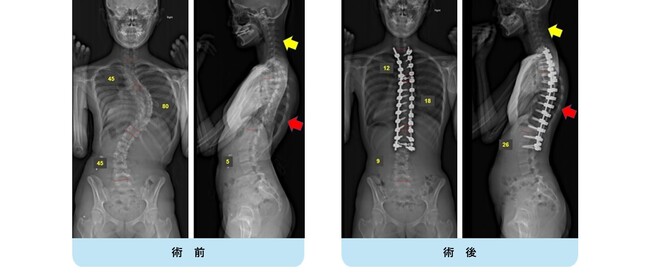

思春期特発性側弯症の全脊椎レントゲンで背骨が大きくSの字に曲がっています。最も曲がっている箇所は80°で、高度側弯に分類されます。後方からの脊柱側弯矯正術で真っ直ぐになっています。

また、側弯の患者さんは一般的にフラットバックと言って背骨の生理的後弯(背中の丸み)が失われています。この症例も胸椎後弯角は5°で典型的なフラットバックを呈しています(正常は20°~30°程度です)。この影響は頸椎の形態にも影響を及ぼし、この症例も頸椎が既に後弯(正常は前弯)しています。(黄色矢印)

ストレートネックという頸椎の前弯が消失して頸部の愁訴が出現する病態は広く知られていますが、更に変形が進行した頸椎と考えて下さい。

以前はこのフラットバック(生理的胸椎後弯の消失)を治すことは困難でしたが、当院では手術方法の様々な工夫により生理的胸椎後弯の復元を行っております。この症例は術後に胸椎後弯角が26°と改善しており、生理的な胸椎後弯が形成されています。さらに頸椎後弯にも良い影響を及ぼし、術後は頸椎前弯化が得られつつあるのが分かります。(黄色矢印)

他、側弯変形は必ず大なり小なりの回旋変形を伴います。脊柱の回旋変形は胸郭(肋骨)の回旋につながり、これにより側弯の患者さんは背中の片方が出っ張っています(多くは右)。リブハンプと言いますが、脊柱変形矯正によりこの回旋変形も改善します。この症例も術前に肋骨がかなり隆起していますが、術後にこの隆起がかなり減じているのが分かります。(赤矢印)

思春期特発性側弯症の全脊椎レントゲンで背骨がSの字に曲がっています。最も曲がっている箇所は52°で、成長終了後も高率にカーブが進行し続けます。50°前後の側弯であれば手術により80%以上まっすぐにすることができます。通常は70%程度の矯正率で良いとされていますが、本来出来るだけまっすぐする手術であり、バランスが損なわれるようなことがなければ我々は矯正率80%を目指しています。

この症例は術後の側弯角は8°で、矯正率は85%でした。また肩バランスも水平で保たれています。また注目すべきは腰の曲がりです。術前のレントゲンをみると腰にも側弯があるのが分かります。(黄色矢印)

腰椎の可動性を残すために、胸椎の側弯に絞って矯正固定を行い腰椎の側弯が引っ張られて改善することを期待しました。術後のレントゲンをみると金属が埋め込まれていない腰椎の側弯が大きく改善しているのが分かります。(黄色矢印)

この症例についても、横から見ると術前に右の背中が肋骨隆起(リブハンプ)により出っ張っています。(赤色矢印)

手術により側弯だけでなく回旋矯正、生理的胸椎後弯形成が成され、術後は右の背中の出っ張りがなくなり生理的な背中全体の丸みが復元されているのが分かります。(赤色矢印)

このように我々は側弯だけでなく、本来の生理的なshapeを取り戻すことを目標に治療を行っています。